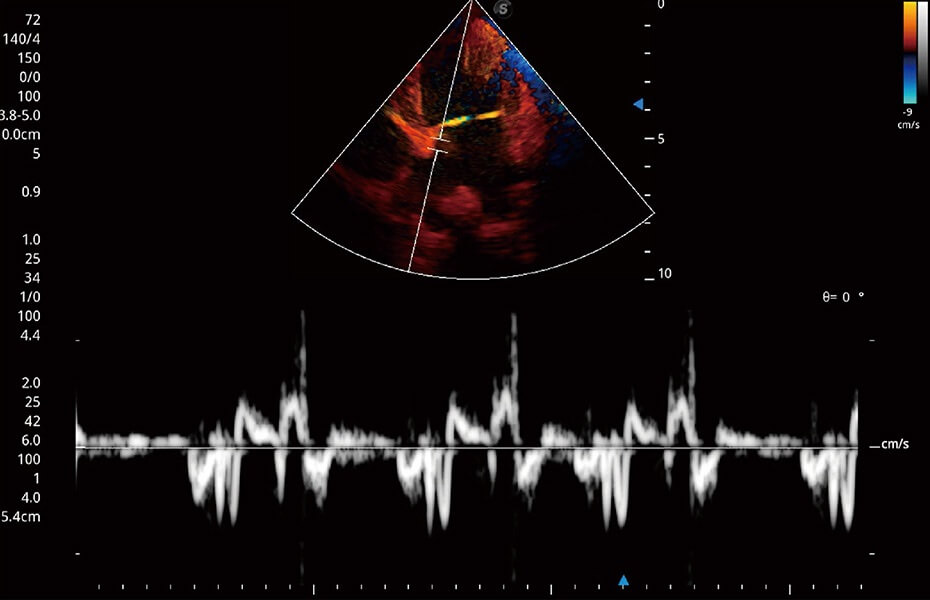

ProPet 60 作為一款高端臺式動物超聲設備,為動物醫(yī)生的日常診斷提供了一系列貼合動物臨床需求、解決臨床實際問題的高級成像功能。憑借全系列高清探頭,滿足醫(yī)生對腹部、心臟、生殖、淺表、肌骨等成像的所有需求,切實幫助您提升檢查效率,提高診斷信心。

動物是人類最親密的朋友和最值得信賴的伙伴。開立醫(yī)療也一直致力于探索動物專用的超聲影像解決方案。 全新推出的ProPet系列,是開立在動物超聲影像智能化、專業(yè)化、精準化的一次跨越式革新。動物不能用言語來表述自己的不適,通過超聲影像,ProPet系列搭建了動物醫(yī)生與不同物種溝通的“橋梁”,為動物醫(yī)生注入了“治愈之力”。